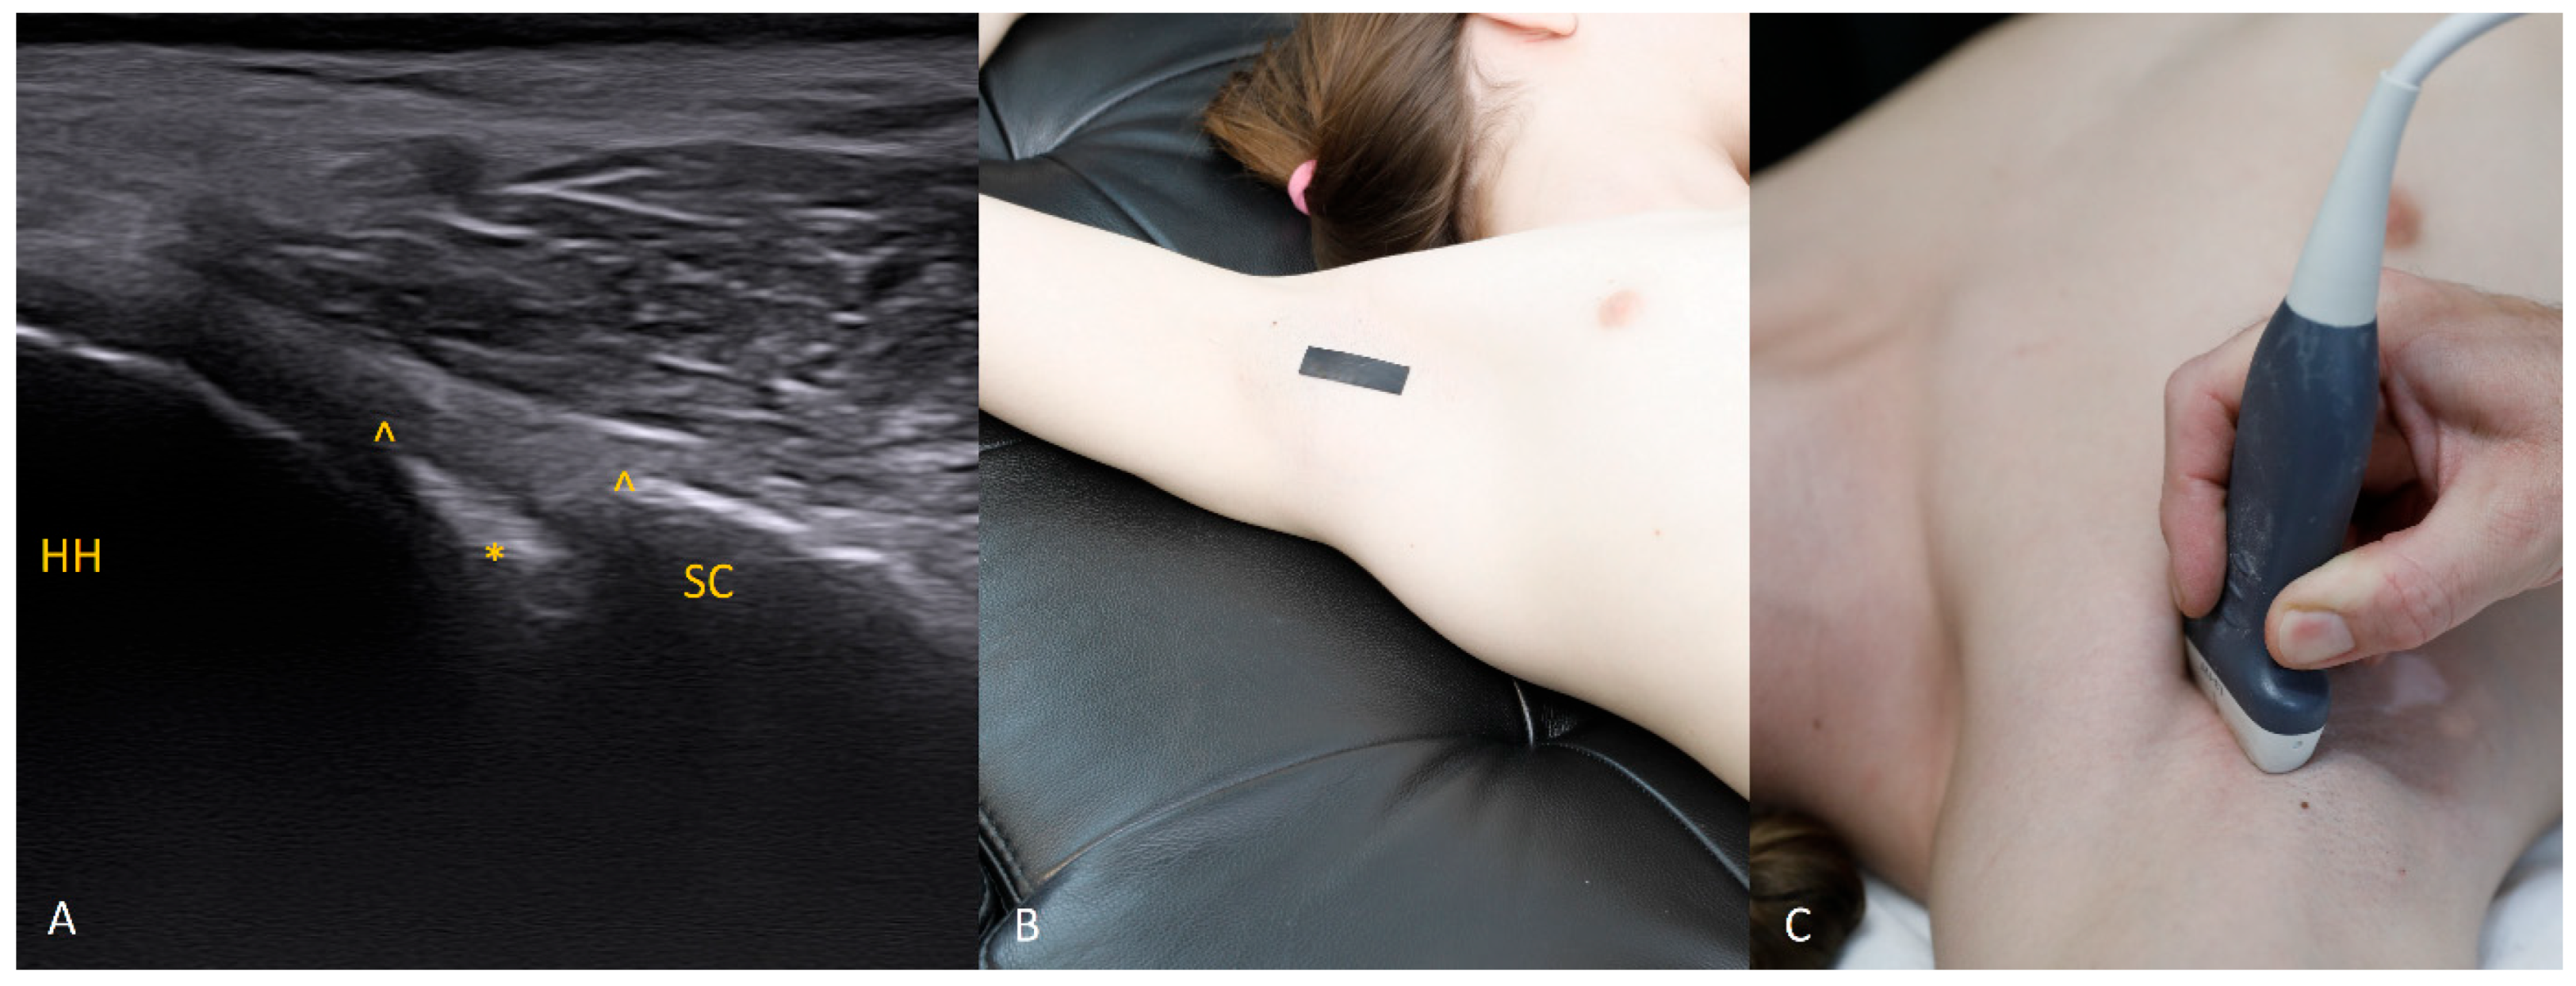

2.3.2. Anterior Segment (3–4 O’clock)

For visualization of the anterior labrum, the transducer is placed horizontally, with the humeral head located laterally and the glenoid rim medially. External rotation of the arm and gentle medial pressure with the transducer help correct scapular tilt and improve acoustic contact. During dynamic assessment, internal rotation may demonstrate subtle medial displacement of the labral edge, which is a useful indicator of early detachment.

Each figure (Figure 1, Figure 2, Figure 3, Figure 4, Figure 5, Figure 6, Figure 7, Figure 8, Figure 9, Figure 10, Figure 11 and Figure 12) illustrates the ultrasonographic appearance of the glenoid labrum at a given clock-face position. Panels: (A) ultrasound image; (B) diagram indicating transducer placement on the patient’s shoulder; (C) clinical photograph of transducer application. Symbols used: ✱ (asterisk), labrum; SC, scapula (bony margin of the glenoid); CR, coracoid process; HH, humeral head; ^, joint capsule; TER MIN, teres minor; IS, infraspinatus; ACR, acromion. Not all abbreviations appear in every figure.

Figure 3. The 3 o’clock position. Typical transducer position and labral appearance. At 3 o’clock, if the patient has substantial muscle mass or is obese, the labrum may be examined with the patient supine. In addition to external rotation and firmer pressure on the medial transducer edge, the supine position helps compensate for the oblique orientation of the scapula relative to the chest wall. The anterior and anteroinferior labrum are the most frequent sites of injury. When looking for signs of damage, pay attention to the labral contour, the presence of fissures that may appear only during dynamic assessment (with rotation), and any medial displacement, which may be fixed (in chronic lesions) or occur only during internal rotation. In that case, during internal rotation the labrum slides medially off the glenoid rim, whereas with external rotation it returns to its proper position (reduction) under tension from the glenohumeral ligaments [8,9,10].